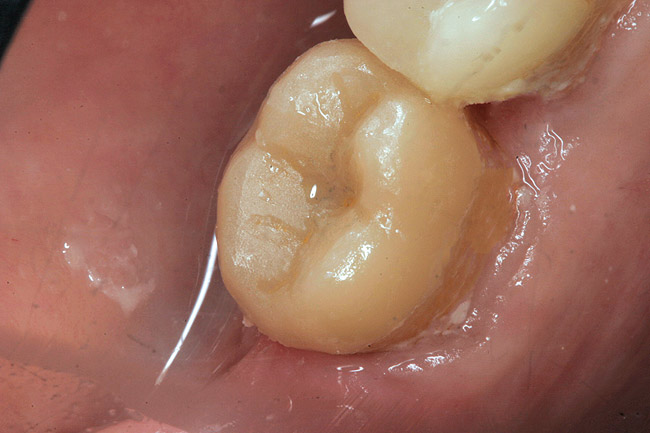

Figure 3  Facial view (Fig 2) and occlusal view (Fig 3) of nonretentive adhesively retained ("table-top") preparation.

Figure 3

A 70-year-old patient presented with symptoms of a cracked tooth scenario, with intermittent pain upon chewing and thermal sensitivity. The diagnosis was supported through various tests, which determined the lower right second molar had an incomplete fracture that extended from the distal marginal ridge to the mesial marginal ridge. After treatment options were presented, an all-ceramic restoration was decided upon. The tooth was prepared for a nonretentive, adhesively retained all-ceramic restoration ("table top" preparation) (Figure 2 and Figure 3). After the preparation was completed a mild self-etching adhesive was applied to the dentin according to the manufacturer's instruction (Figure 4). There was little concern, if any, of the adhesive reaching the band of exposed enamel. The adhesive was light-polymerized for 5 seconds to secure the layer to the dentin (Figure 5). To eliminate the oxygen-inhibited layer a water-soluble gel was applied to the adhesive and further light-polymerization was completed (Figure 6 and Figure 7). For direct digital scanning cases in which a powdering technique is employed for image capture, it may be more difficult to remove the powder after scanning if the oxygen-inhibited layer is still present.